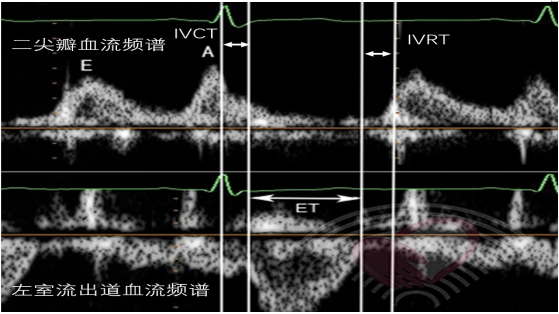

(4)右心室Tei指数(RV MPI):即为多普勒心肌工作指数,选择脉冲多普勒技术(PW),在右室流入道和流出道取样,并连接心电图以获得相应的数据。或根据三尖瓣环组织多普勒(TDI)测定三尖瓣关闭-开放时间(TCO),TCO=等容收缩期(IVCT)+射血时间(ET)+等容舒张期(IVRT)。

RV MPI=[等容收缩时间(IVCT)+等容舒张时间(IVRT)]/射血时间(ET),但实践中常规规定RV MPI=[三尖瓣反流时间(TCO)-右室流出道射血时间(ET)]/右室流出道射血时间(ET)。RV MPI的PW测量大于0.4或TDI测量大于0.55一般认为右心心肌功能的恶化。

图片

图17. RV MIP的测量

注:上图为PW测量,RV MIP=(TCO-ET)/ET,图为TDI测量,(IVRT+IVCT)/ET

①PW下在心尖五腔心切面测量取样容积放置于左室流出道与二尖瓣口之间,获得收缩期左室流出道及舒张期二尖瓣前向血流的速度图图31。测定二尖瓣关闭至主动脉瓣开放的时间为IVCT,主动脉瓣血流频谱开始至频谱末时间为左心室射血时间(ET),主动脉关闭至二尖瓣开放的时间为IVRT。

图31. PW测量LV MPI,Tei=(IVCT+IVRT)/ET